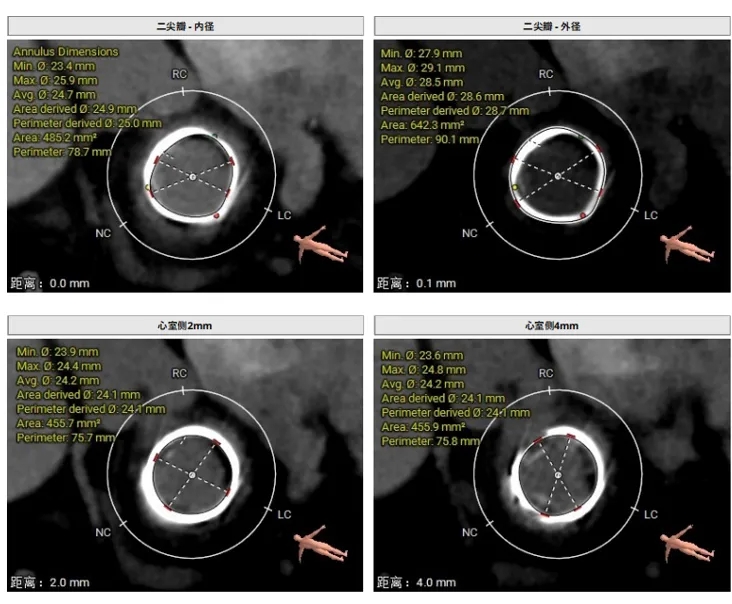

瓣架内径:25.0mm

瓣架外径:28.7mm

心室侧2mm:24.1mm

心室侧4mm:24.1mm

心室侧6mm:23.9mm

瓣架高度:约17.0mm

工作角度-瓣环切线位:RAO39°CRA38°

LVOT:22.6mm,NEO-LVOT:23.5mm,模拟植入介入瓣后,流出道剩余面积尚可